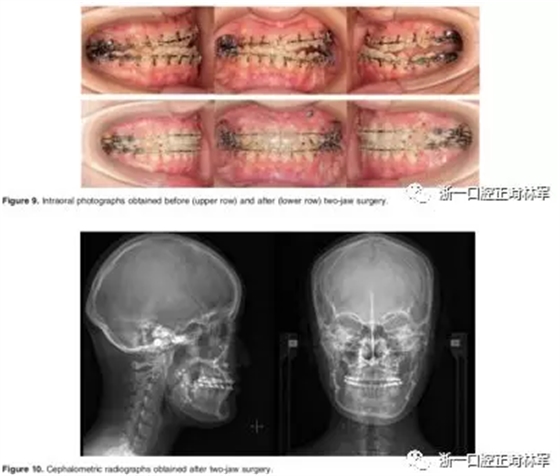

第三阶段:治疗开始26个月后,进行双颌手术。术前持续使用咬合板。行Le Fort I型截骨术和下颌骨矢状劈开术(SSRO),以矫正上颌咬合偏斜、下颌偏斜。